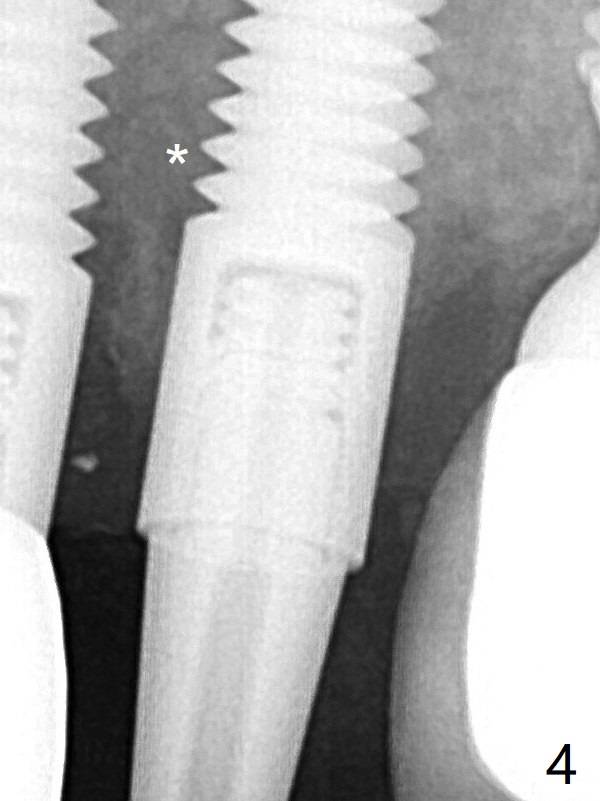

A 4x20 mm tissue-level implant is placed with > 60 Ncm, followed by tightening a 3.5x5 mm abutment (Fig.4); the mesiobuccal defect being filled with Vera Graft (*).   It appears that the implant should have been placed deeper (Fig.6: 5 months postop).  The unipost is bonded with Relyx Ultimate prior to reprep and impression.